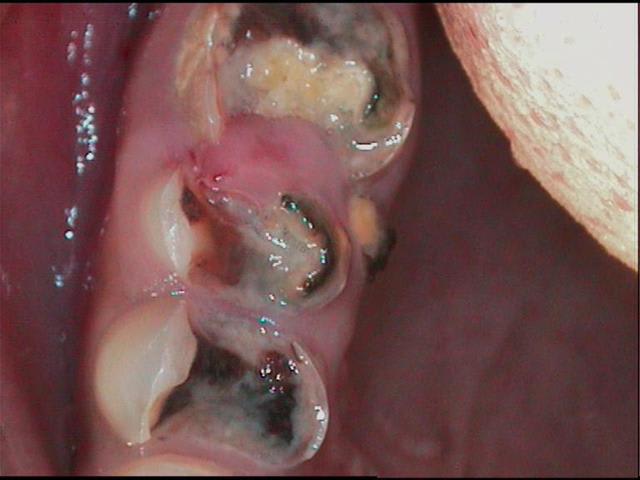

13 ans, je vous livre en vrac et dans n'importe quel sens

je m'en vais donc naviguer quelques temps entre pulpites et nécroses, calmer les pleurs, resorber les granulomes, ré équilibrer le "risque carieux"

j'ai passé les détails, aucune dent indemne de toute manière, tout est comme ça , les inc md itou

techniquement je dois etre loyal, les photos font reculer, j'ai reculé aussi en bouche, mais c'est plus impressionant au premier abord, dans le détail tout peut se jouer comme le montre cette radio

alors: les pulpites et granulomes en prems, ensuite les endos inévitables, ensuite des verre iono ou eugenates partout, ré équilibrer le risque et motiver, ensuite caler l'occlusion avec les 8 pm dans un premier temps(parceque là j'y pige rien) ensuite l'ortho (parceque là c'est pas présentable)enfin toutes ces sortes de chose quoi...